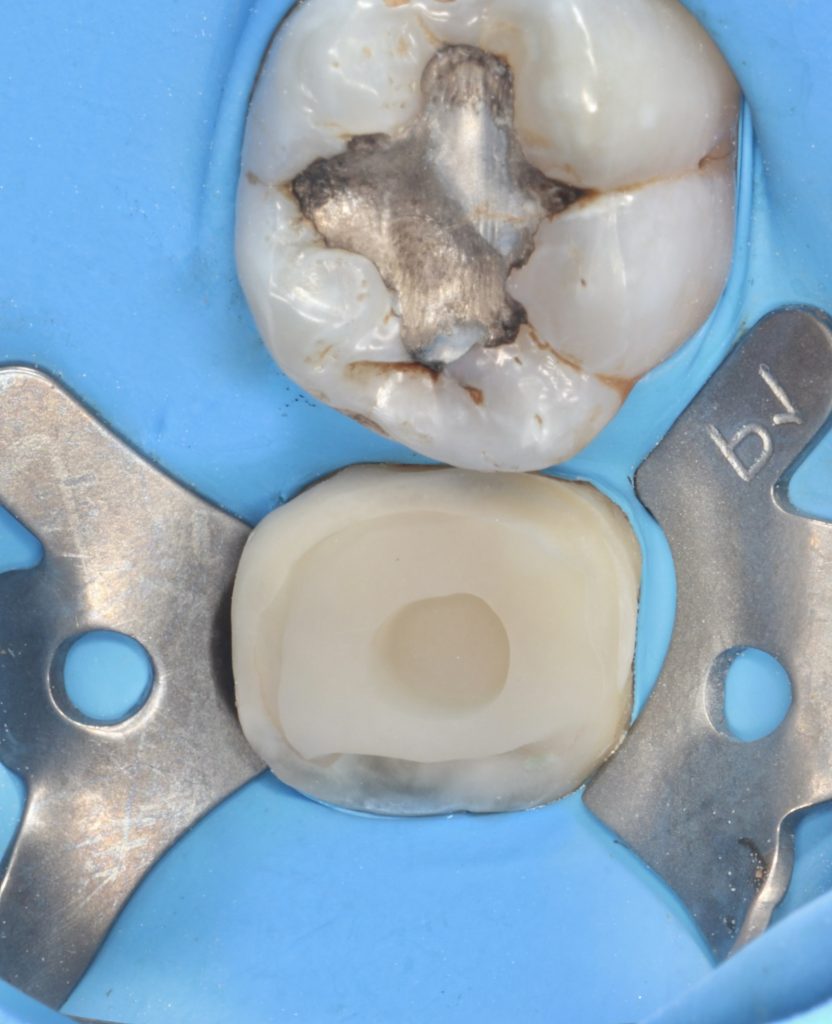

Fiber materials were used to strengthen the furcation area prior to the biobase.The patient’s high saliva density made it necessary to use an intraoral scanner on a rubber dam

In this case where tissue loss is high, we thought that using a resin-containing ceramic block would increase the strength of the tooth in the long term.

Voco Grandio A2 HT (Highest filler content 86 % w/w )

3.Fiber reinforced bio base

4.Resin-ceramic overlay